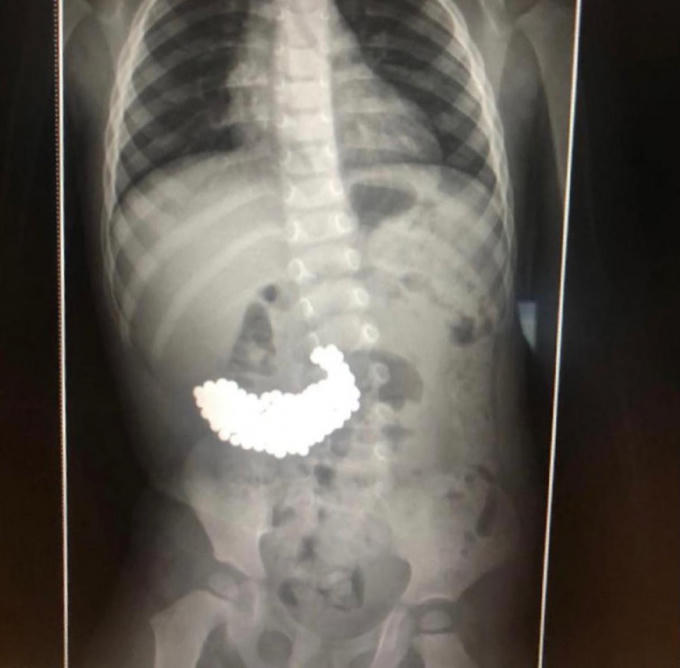

Sau ca phẫu thuật bằng thiết bị nội soi suốt 2 giờ đồng hồ các bác sĩ đã lấy ra tổng cộng 209 viên bi kim loại có gờ sắc nhọn, có thể đâm thủng niêm mạc dạ dày bất cứ lúc nào.

209 viên bi nam châm được lấy ra khỏi dạ dày của cậu bé. Ảnh: News.com.au